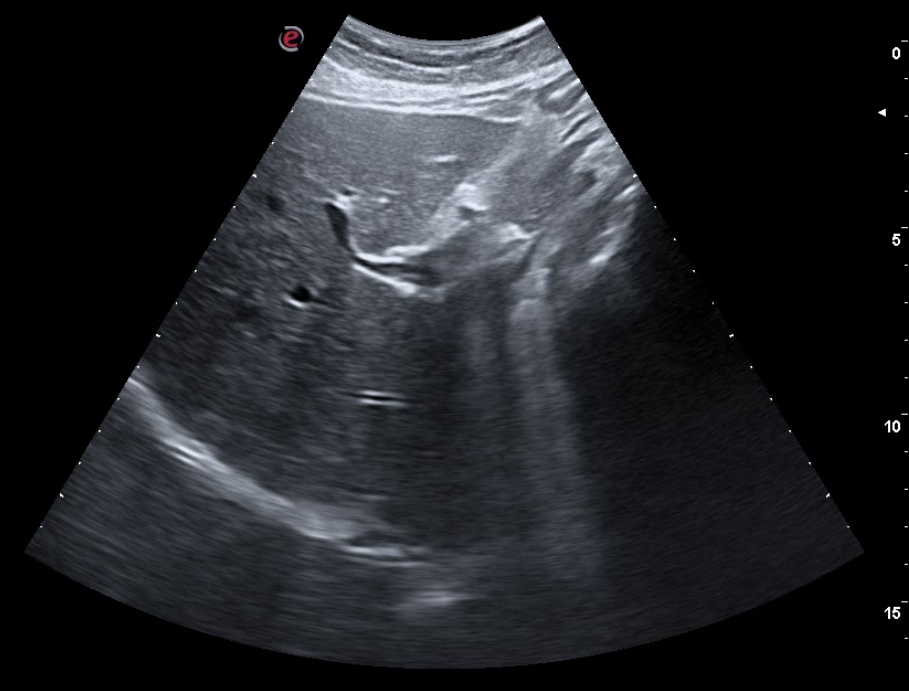

En consulta decidimos realizar ecografía clínica abdominal mostrando hígado de ecoestructura y tamaño adecuados, con vena porta y suprahepáticas permeables, con vesícula biliar repleccionada sin ecos en su interior, páncreas visible sin alteraciones, riñones con buena diferenciación córtico-medular con vejiga reflexionada sin ecos en su interior, útero involucionado, y una masa dependiente de fosa ilíaca derecha de 5×5 cm de ecoestructura similar a un riñón, correspondiente al área explorada.